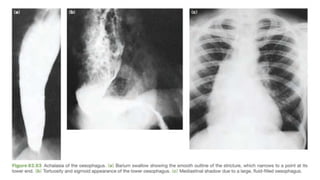

 Barium swallow: smooth narrowing

with proximal esophageal dilatation.

Bird Beak Sign

Diagnostic approach &investigations  Barium swallow: smooth narrowing with proximal esophageal dilatation.  High-resolution manometry: uncoordinated abnormal contraction patterns, which may be important in predicting the outcome of treatment.

• #18 Barium swallow shows a smooth narrowing (inverted bird beak appearance) with evidence of proximal oesophageal dilatation High-resolution manometry recognizes uncoordinated abnormal contraction patterns, which may be important in predicting the outcome of treatment. The gastric gas bubble is usually absent. endoscopy by fnding a tight cardia and food residue in the esophagus.